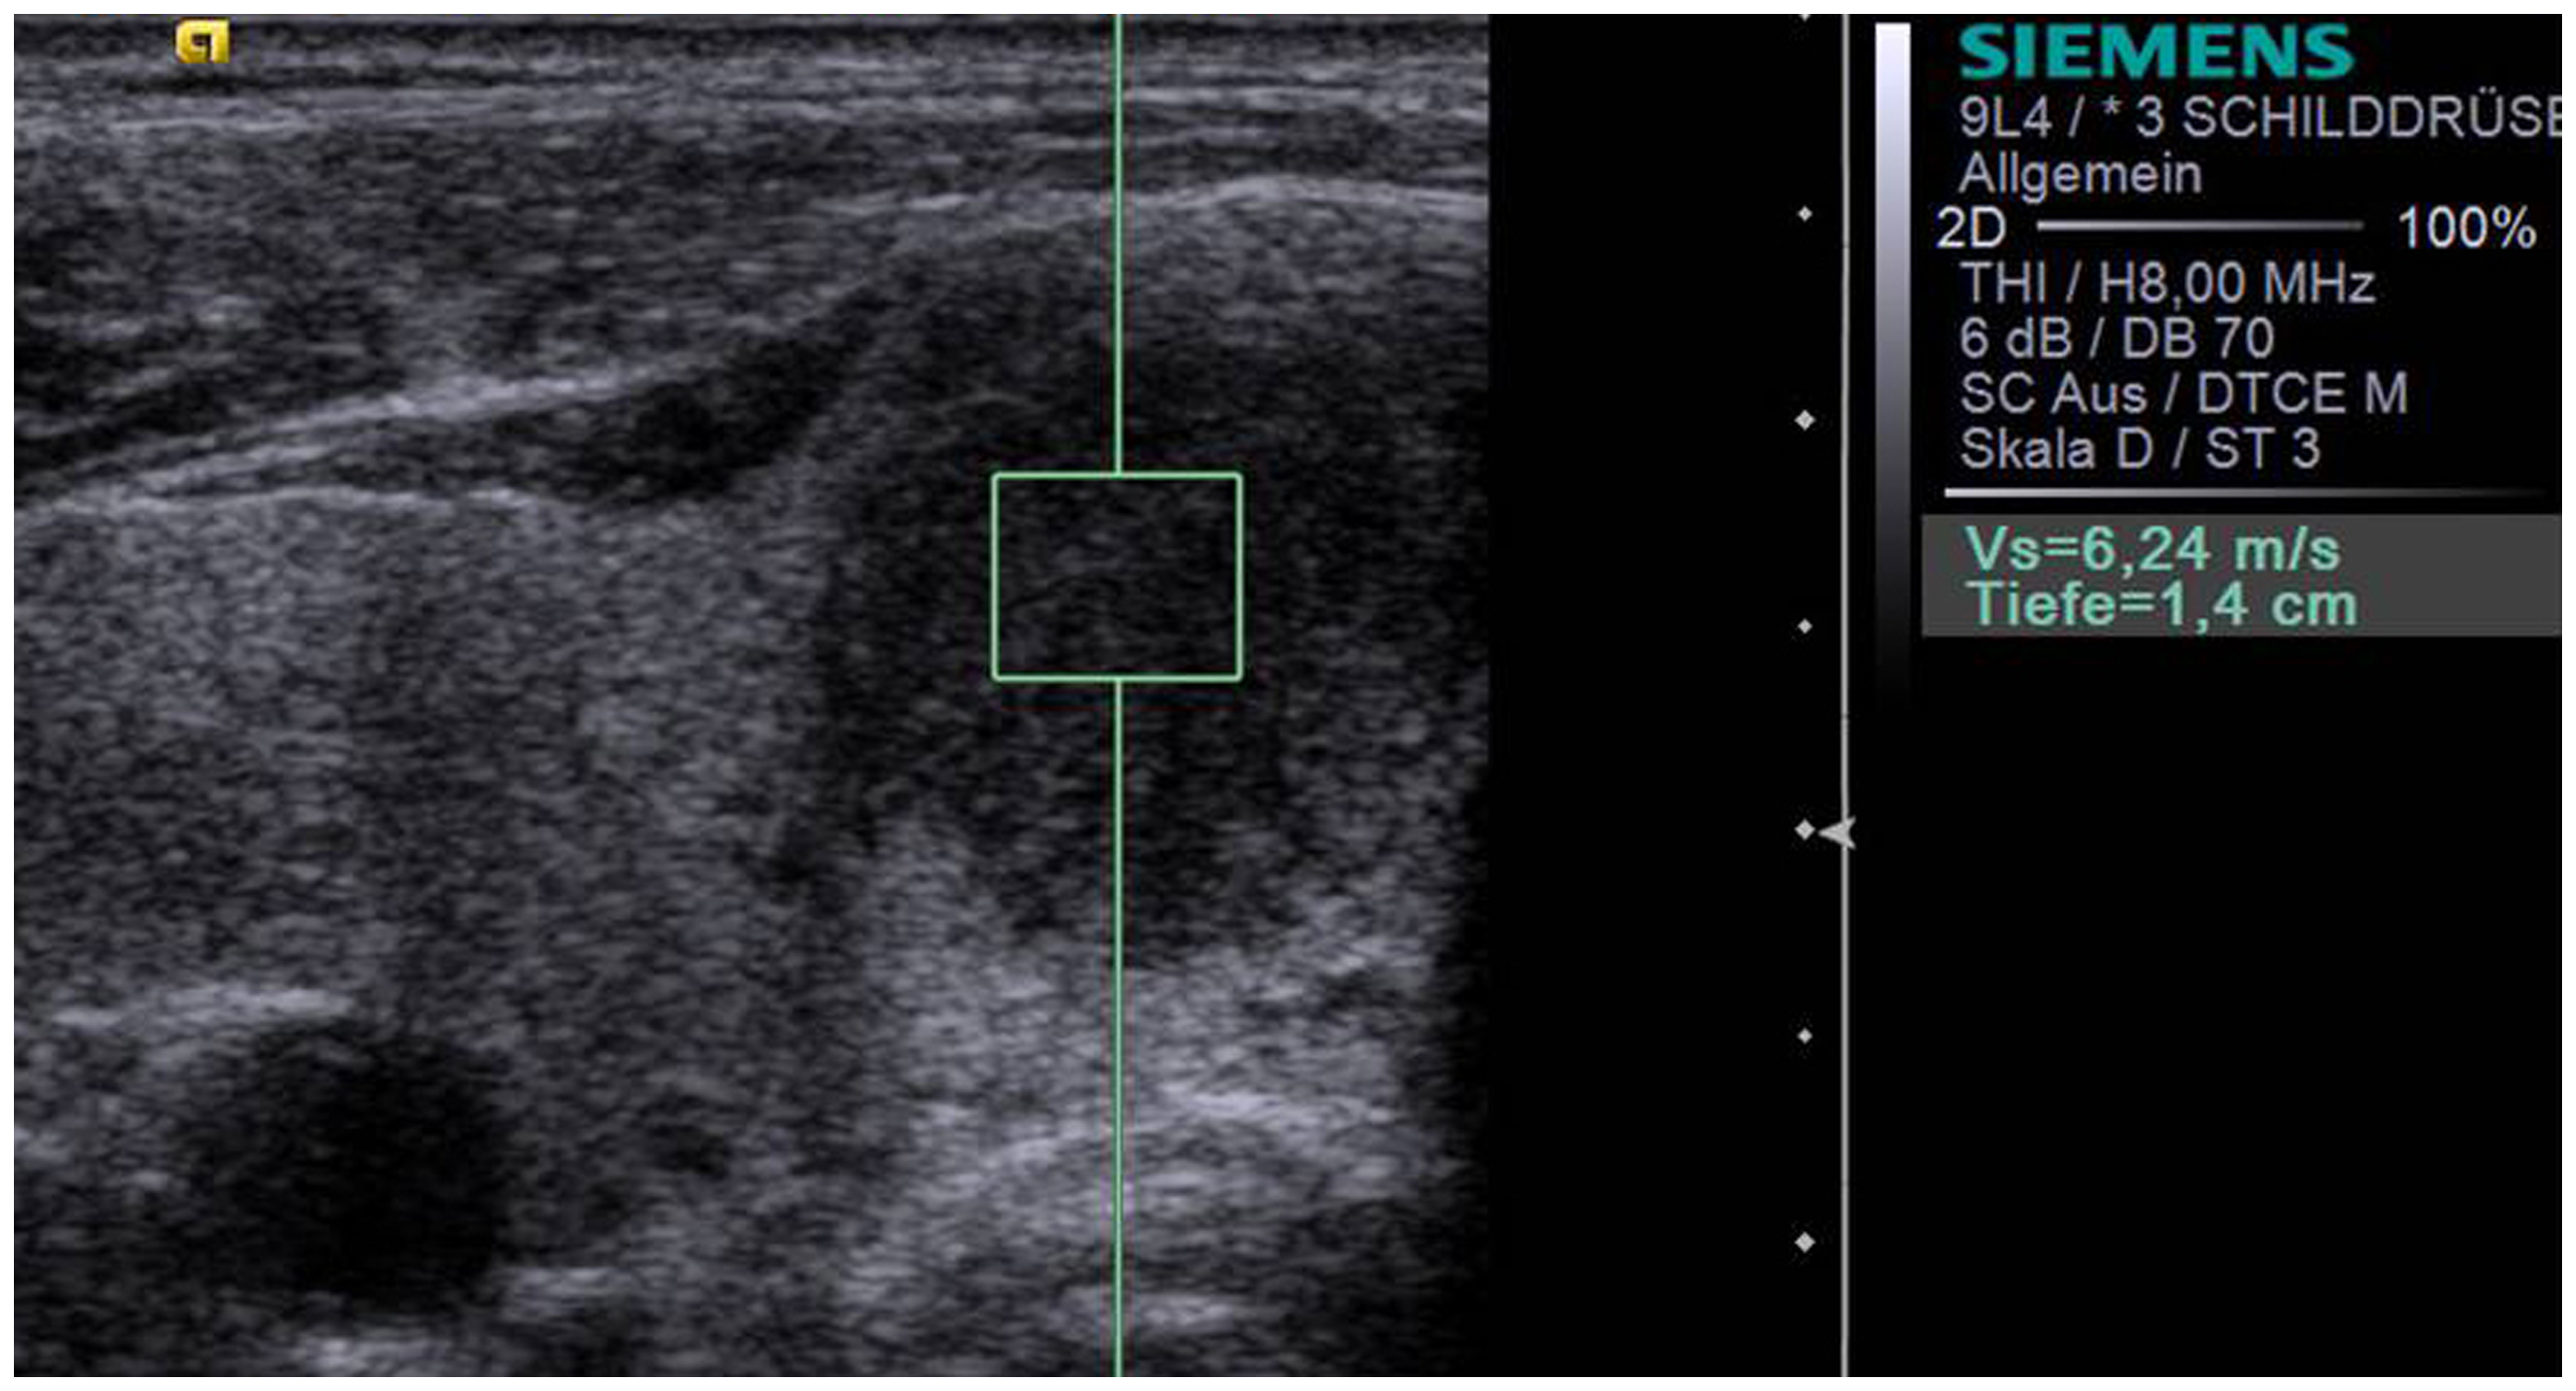

전단파 탄성 영상(SWEI)은 음향 방사력을 이용하여 조직 깊숙한 곳에 '밀기'를 유도한다. 이 밀기로 인해 발생하는 교란은 전단파 형태로 조직을 통해 측면으로 이동한다. 초음파나 MRI 같은 영상 방식을 사용하여 파동이 다양한 위치에 도달하는 속도를 관찰함으로써, 조직의 강성을 추론할 수 있다. "탄성 영상"과 "탄성계측법"은 같은 의미이므로, 전단파를 이용해 탄성 맵을 나타내는 SWEI라는 용어는 종종 SWE로 대체된다.SWEI와 ARFI의 주요 차이점은 SWEI는 빔 축에서 측면으로 전파되는 전단파를 이용하여 탄성 맵을 생성하는 반면, ARFI는 밀기 빔의 축에서 탄성 정보를 얻고 여러 번의 밀기를 통해 2차원 강성 맵을 생성한다는 것이다.[7] ARFI에는 전단파가 관여하지 않으며, SWEI에는 축 방향 탄성 평가가 없다. SWEI는 초음속 전단 영상(SSI)에서 구현된다.

초음속 전단파 영상(SSI)은 조직 강성의 정량적이고 실시간적인 2차원 지도를 제공한다.[8][9] SSI는 SWEI를 기반으로 하며, 음향 방사력을 사용하여 관심 조직 내부에 '밀기'를 유도하여 전단파를 생성하고, 결과적인 전단파가 조직을 얼마나 빠르게 통과하는지로부터 조직의 강성을 계산한다. 국소 조직 속도 지도는 기존의 스펙클 추적 기술로 얻으며, 조직을 통과하는 전단파 전파의 전체 동영상을 제공한다. SSI에는 두 가지 주요 혁신이 있다. 첫째, SSI는 여러 번의 거의 동시적인 밀기를 사용하여 초음속으로 매체를 통과하는 전단파의 원천을 생성한다. 둘째, 생성된 전단파는 초고속 영상 기술을 사용하여 시각화된다. 역 알고리즘을 사용하여 매체의 전단 탄성은 파동 전파 동영상으로부터 정량적으로 매핑된다. SSI는 1초에 10,000 프레임 이상으로 깊숙한 장기를 촬영할 수 있는 최초의 초음파 영상 기술이다. SSI는 조직의 기계적 특성을 설명하는 일련의 정량적 및 생체 내 매개변수, 즉 영률, 점도, 이방성을 제공한다.이 접근 방식은 유방, 갑상선, 간, 전립선 및 근골격계 영상에서 임상적 이점을 입증했다. SSI는 여러 개의 고해상도 선형 변환기를 사용하여 유방 검사에 사용된다.[10] 대규모 다기관 유방 영상 연구에서 전단파 탄성 영상이 표준 B-모드 및 컬러 모드 초음파 영상의 해석에 추가될 때 유방 병변의 분류[12]에서 재현성[11]과 상당한 개선이 모두 입증되었다.

순간 탄성 영상(Transient elastography)은 조직에 순간적으로 기계적인 변형력을 가해 조직이 변형된 정도를 통해 조직의 탄성도를 영상화하는 기술이다. 프로브에 모터로 움직이는 진동자를 부착해 조직에 전단 파동을 일으키고, 여기서 일어난 변화를 도플러 영상에 주로 이용하는 펄스파 초음파 영상 기법으로 관측한다[40]. 대표적인 예로 간경변을 진단하기 위해 이용하는 경우가 있다[41].1990년대 후반에 처음 도입되었을 때 시간 분해 펄스 탄성 영상법이라고 불렸다.[15] 이 기술은 조직에 전단파를 유도하는 데 사용되는 과도한 기계적 진동에 의존한다. 전단파의 전파는 초음파를 사용하여 추적하여 영률을 추론하는 전단파 속도를 평가하며, 이는 균질성, 등방성 및 순수 탄성(E=3ρV²)의 가설 하에 수행된다. 순간 탄성 영상이 조화 탄성 영상 기술에 비해 갖는 중요한 장점은 전단파와 압축파의 분리이다.[16] 이 기술은 1차원으로 구현될 수 있으며,[17] 초고속 초음파 스캐너의 개발이 필요한 2차원으로 구현될 수도 있다.[18]